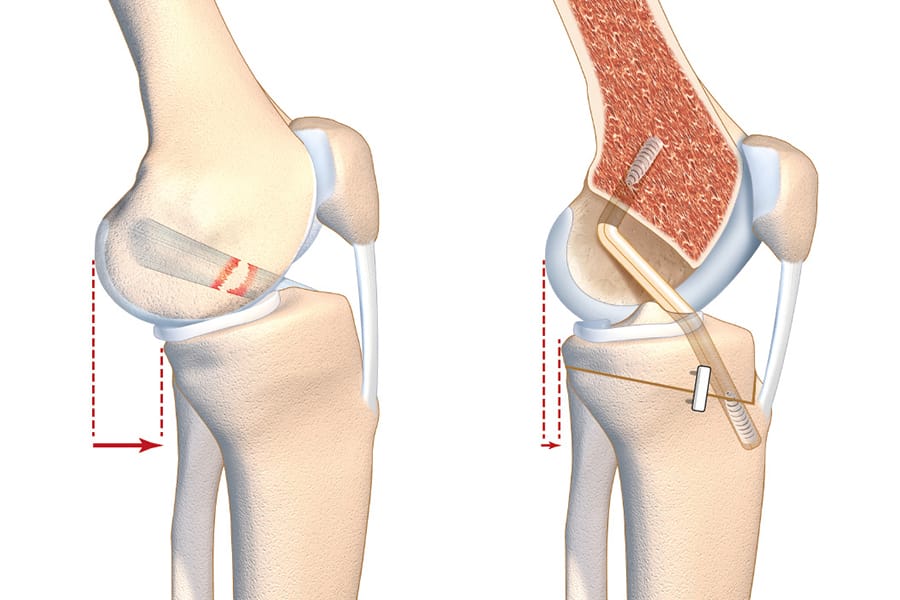

Technique Interaction entre ligament croisé antérieur et pente tibiale : quelle place pour l’ostéotomie sagittale ? , David Mazy Département de chirurgie orthopédique, Lyon Ortho Clinic, Clinique de la Sauvegarde, 29 Avenue des Sources, 69009 Lyon, France 🖂 david.mazy27@gmail.com , Chiara Biatti Département de chirurgie orthopédique, Lyon Ortho Clinic, Clinique de la Sauvegarde, 29 Avenue des Sources, 69009 Lyon, France , Simone Romano Département de chirurgie orthopédique, Lyon Ortho Clinic, Clinique de la Sauvegarde, 29 Avenue des Sources, 69009 Lyon, France , Guillaume Demey Lyon Ortho Clinic - Clinique de la Sauvegarde, 29B avenue des Sources, 69009 Lyon, France , David Dejour Lyon-Ortho-Clinic - Clinique de la Sauvegarde, 8, avenue Ben Gourion, 69009 Lyon, France 🖂 dejour.secretariat@lyon-ortho-clinic.com N°338 - Novembre 2024 ● 27 min de lecture